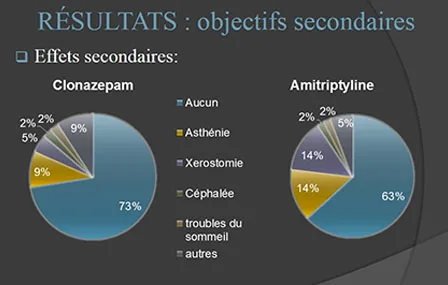

Douleurs oro-faciales multiples - Différencier les diverses etiopathogénies

Auteurs : Eve MALTHIERY, Said KIMAKHE Institution : CHU, département de Chirurgie Buccale Nantes Concepts et mots clés Douleur orofaciale…

Lire la suite →